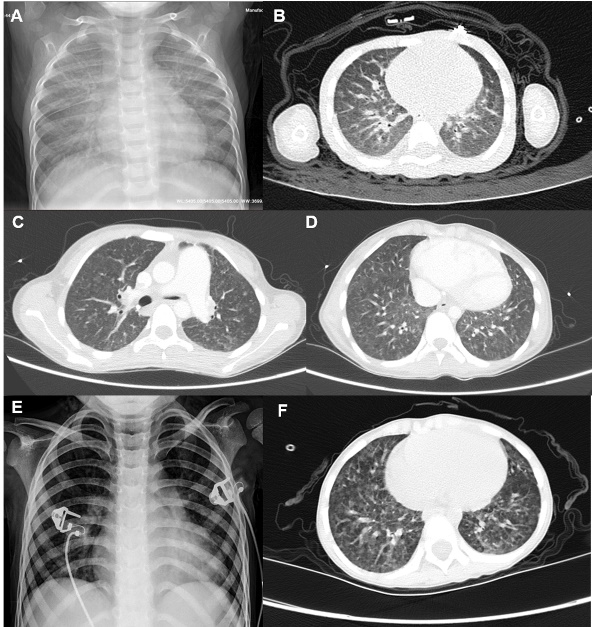

胸部影像学资料见图 1所示,患儿1胸片两肺纹理增多增粗,见片絮影;胸部HRCT见条絮影及网格样改变。患儿2胸部HRCT表现为两肺间质增厚,弥漫小片絮状磨玻璃影。患儿3胸片两肺片絮状密度增高影,胸部HRCT见两肺透亮度欠均匀,弥漫性小斑片状、结节状密度增高影。3例患儿行心脏超声检查,提示不同程度的肺动脉高压,其中2例合并三尖瓣返流,1例合并心包积液。3例患儿均行头颅CT或头颅MRI,未见明显异常。

A:患儿1胸部X线片示两肺纹理增多增粗、片絮影;B:患儿1胸部HRCT示条絮影及网格样改变;C、D:患儿2胸部HRCT示两肺间质增厚、弥漫小片絮状磨玻璃影;E:患儿3胸部X线片示两肺片絮状密度增高;F:患儿3胸部HRCT示两肺弥漫性小斑片状、结节状密度增高 图 1 MAHCC合并呼吸衰竭患儿胸部影像学表现